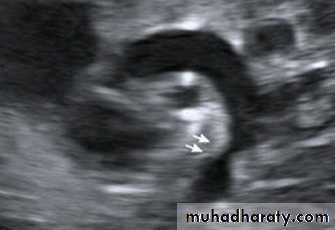

Echocardiography shows the site and degree of coarctation, presence of left ventricular hypertrophy, and aortic valve morphology and function

3-Echocardiography

The location and size of the atrial defect are readily appreciated by two-dimensional scanning . The shunt is confirmed by pulsed and color flow Doppler .